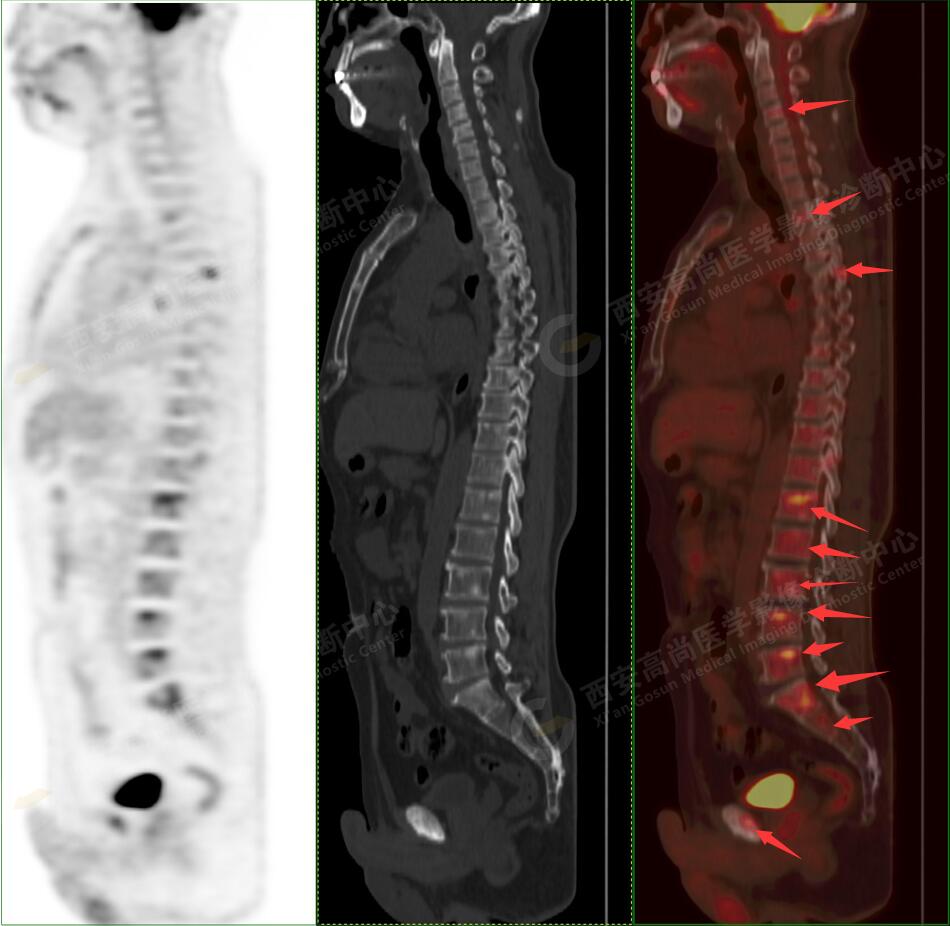

2.以下為全身多發(fā)轉移灶

5.右側肱骨上段、左側肩胛骨、右側鎖骨胸骨端、胸骨、雙側多發(fā)肋骨、脊柱多發(fā)椎體及附件、雙側髂骨、雙側髖臼、雙側恥骨、雙側肱骨上段多發(fā)成骨性病變,呈不同程度FDG代謝異常增高,考慮為多發(fā)骨轉移瘤。

以上病變符合:T4N3M1c,ⅣB期(UICC/AJCC,2018年第8版肺癌TNM分期)。